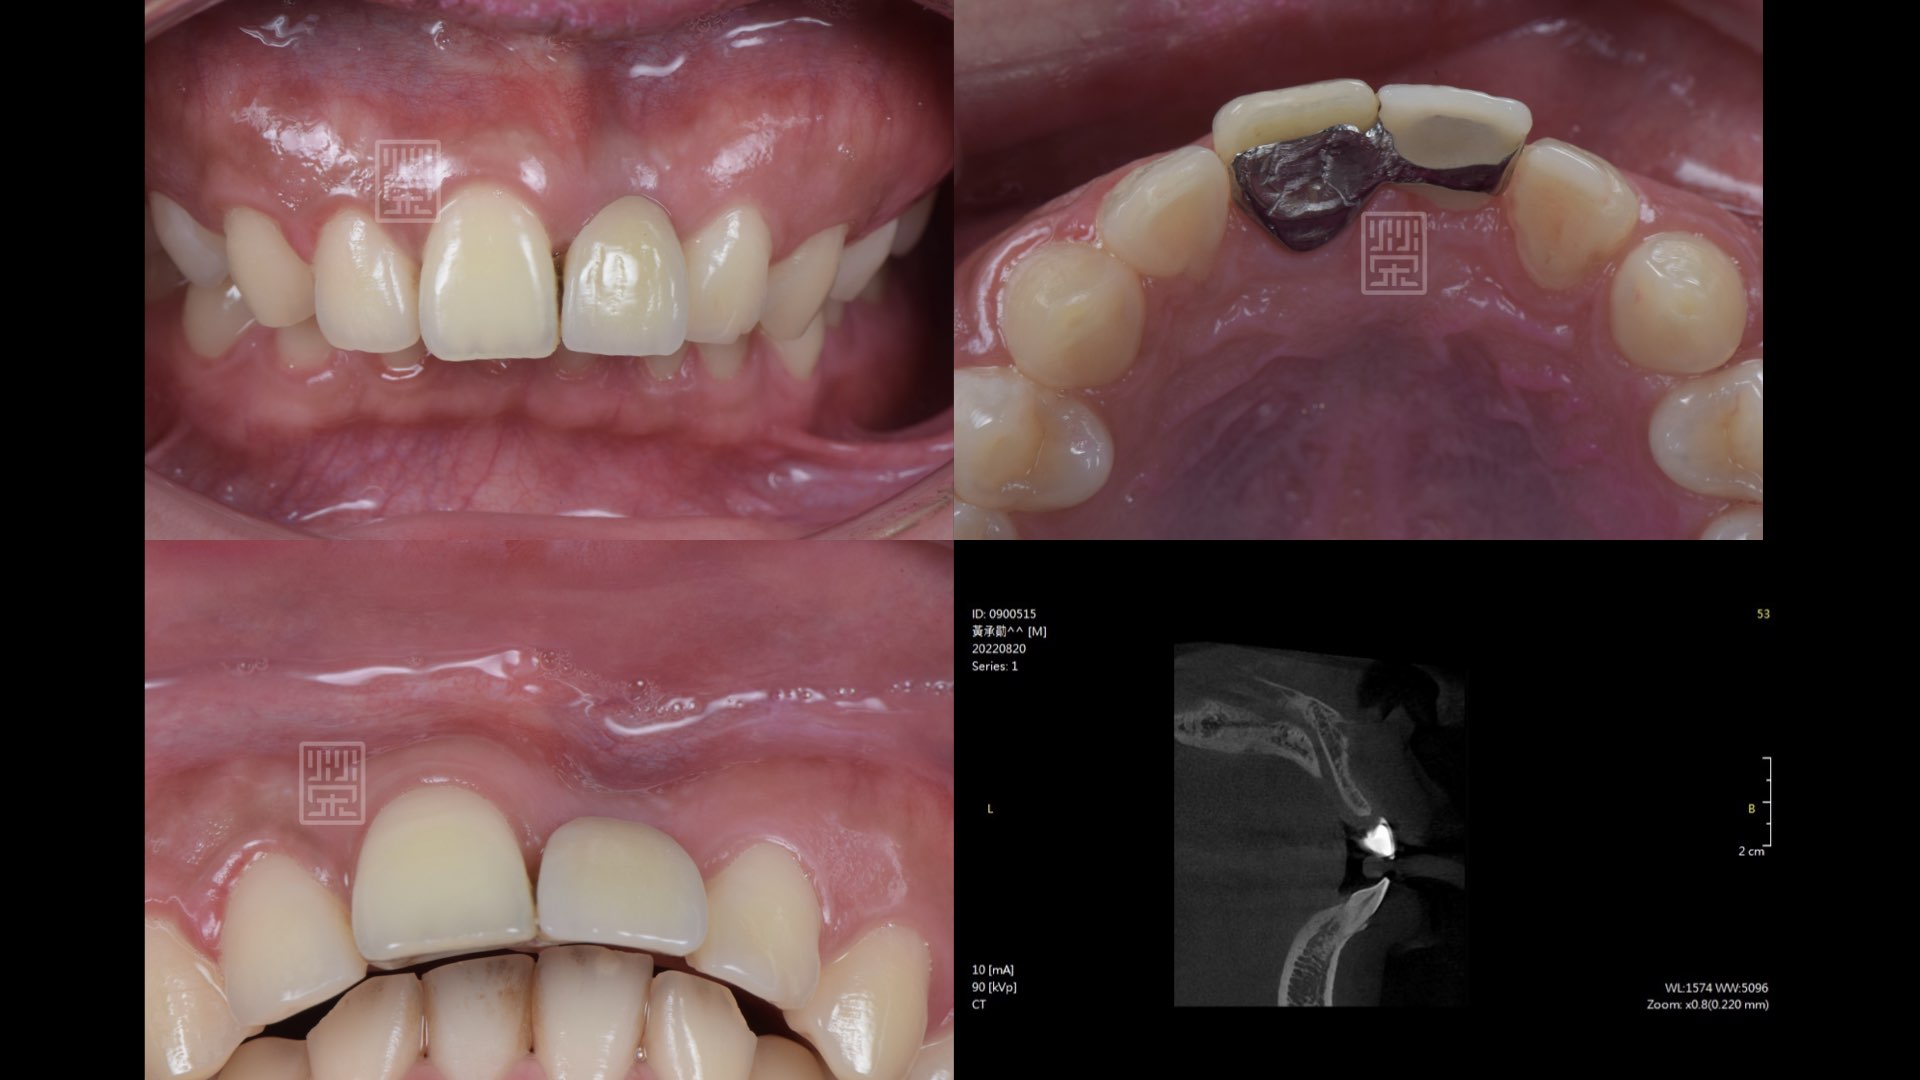

植牙與再次補骨

接出植牙支台

植牙全瓷冠

植牙完成